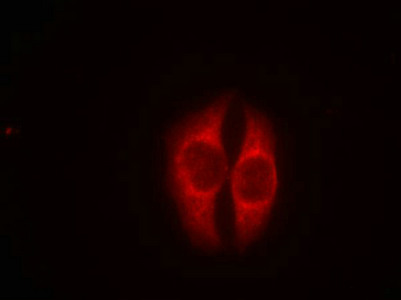

圖片:

應(yīng)用范圍:ELISA,WB,IF

Application Recommended Dilution WB 1:500-1:1000 IF 1:100-1:200 -

亞細(xì)胞定位:Cytoplasm. Nucleus. Nucleus, PML body. Endoplasmic reticulum. Mitochondrion matrix. Cytoplasm, cytoskeleton, microtubule organizing center, centrosome.; [Isoform 1]: Nucleus. Cytoplasm. Note=Predominantly nuclear but localizes to the cytoplasm when expressed with isoform 4.; [Isoform 2]: Nucleus. Cytoplasm. Note=Localized mainly in the nucleus with minor staining in the cytoplasm.; [Isoform 3]: Nucleus. Cytoplasm. Note=Localized in the nucleus in most cells but found in the cytoplasm in some cells.; [Isoform 4]: Nucleus. Cytoplasm. Note=Predominantly nuclear but translocates to the cytoplasm following cell stress.; [Isoform 7]: Nucleus. Cytoplasm. Note=Localized mainly in the nucleus with minor staining in the cytoplasm.; [Isoform 8]: Nucleus. Cytoplasm. Note=Localized in both nucleus and cytoplasm in most cells. In some cells, forms foci in the nucleus that are different from nucleoli.; [Isoform 9]: Cytoplasm.